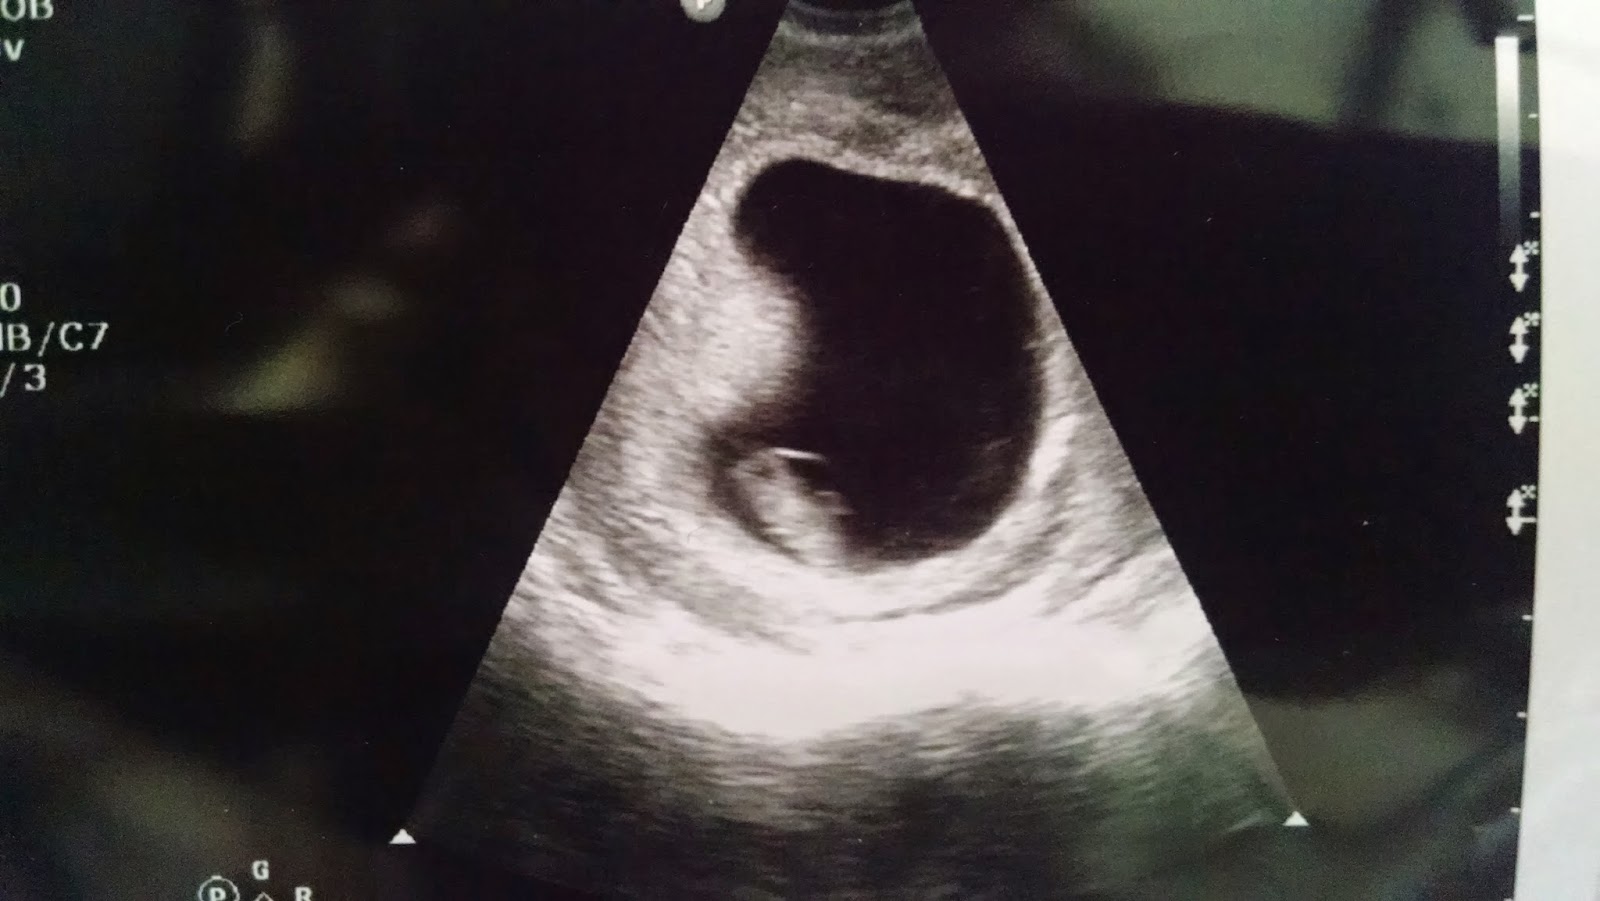

Movement/Symptoms: baby boy is a dancing/karate machine. If I do things he doesn't like, he is FAST to let me know. I can't wait for husband to feel him!

Gender: it's a boy! we're going to name him Charles. the middle name is up for debate lol

Looking forward to: We see Bee Charlie!! a week from Monday!! 8 ish days! ahh